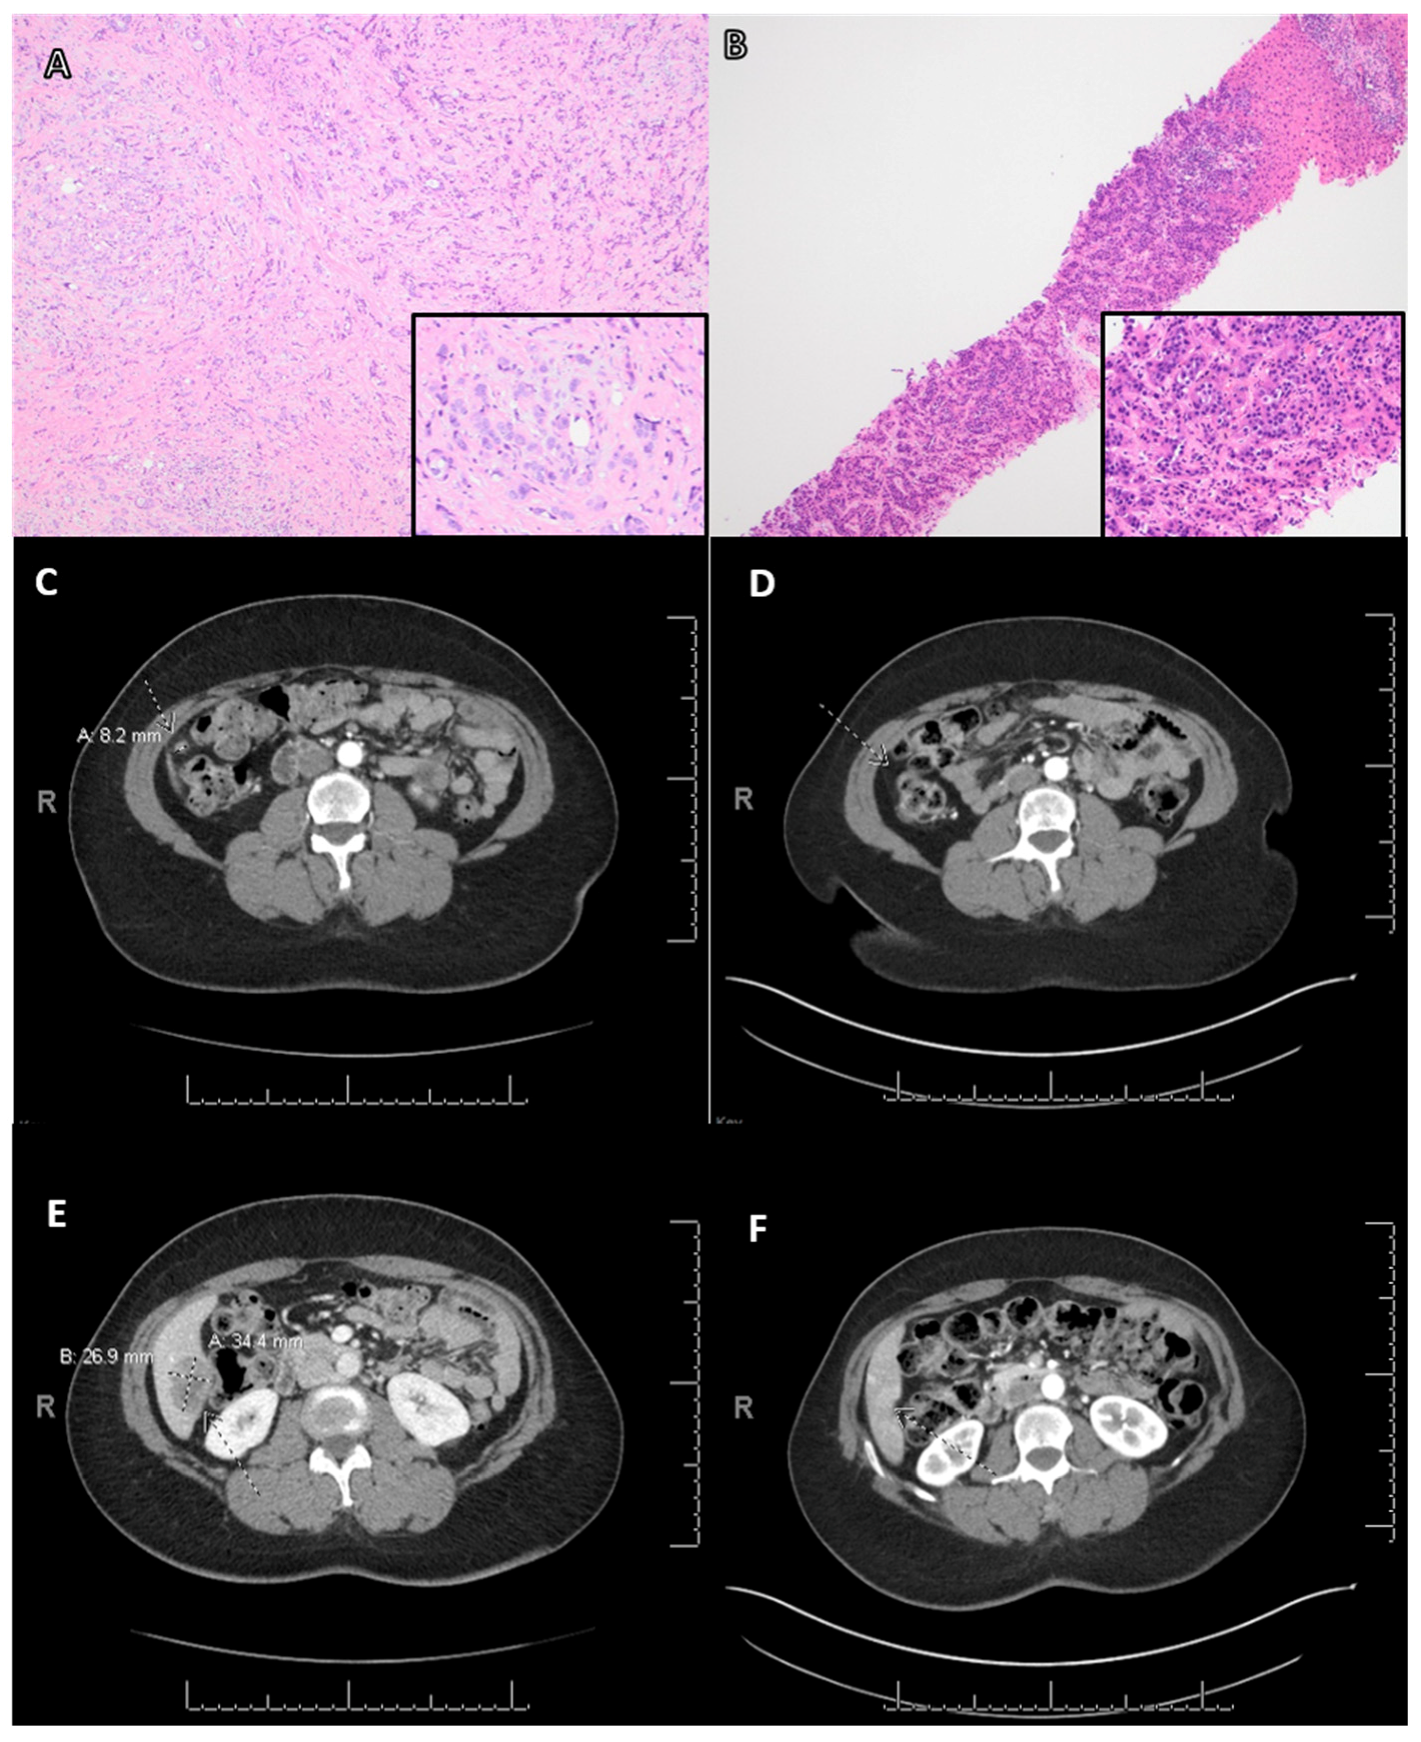

| Case | Age | Primary Tumor a | Lymph Node Status | History of Treatment | NGS g | LOH (%) | TMB (Muts/Mb) | PARPi d | Follow-Up e (Month) | Clinical Response f | ||||||||

|---|---|---|---|---|---|---|---|---|---|---|---|---|---|---|---|---|---|---|

| Diagnosis | NG | ER | PR | HER2 | Surgery b | Systemic Therapy c | Radiation | Method | HRR Gens | Non-HRR Gens | ||||||||

| 1 | 46 | IC-NST | 2 | Pos | Pos | Neg | Neg | PM | Docet Cytoxan Tamox | Yes | IVD | PALB2 p.Y1108fs*6 PALB2 p.K480fs*6 | Rad21 Amplified RARA p.M284I | N/A | 3 | O | 7 | PR |

| 2 | 59 | IC-NST | 3 | Neg | Neg | Neg | Neg | TM | Docet Cytoxan Doxor Pembro | Yes | IVD | BRCA1 p.V757fs*8 | PTEN loss MYC amplified CDKN2A/B loss EP300 truncation intron 27 FAS loss GATA6 amplified LRP1B p.R441* MCL1 amplified NUP93 p.R709T TP53 p.L257P | N/A | 5 | O | 40 | DF |

| 3 | 20 | IC-NST | 3 | Neg | Neg | Neg | Pos | TM | Doxor Cytoxan Carbo Taxol | Yes | IVD | BRCA1 p.R1751 | CTNNA1 p.E686fs*39 RB1 splice site 2063–2106+20del64 TP53 p.R175H | N/A | 1 | O | 6 | SD |

| 4 | 60 | IC-NST | 3 | Pos | Pos | Neg | Pos | TM | Doxor Carbo Tamox | Yes | IVD | BRCA1 p.C903fs*97 FANCA p.E63* | FGF12 amplified MYC amplified PIK3CA p.P104del SF3B1 p.K700E SOX2 amplified | N/A | 6 | O | 3 | PD |

| 5 | 47 | IC-NST | 3 | Neg | Neg | Neg | Pos | TM | Atezo Nab-p | Yes | IVD | BRCA1 p.K1183R VUS | AKT1 p.E17K TP53 p.C141Y NF1 p.E1334* | N/A | N/A | O | 4 | PD |

| 6 | 59 | IC-NST | 2 | Neg | Neg | Pos | Pos | TM | Docet Herce Pertu | Yes | WES | BRCA2 p.V188M VUS CHEK2 p.Y139H VUS | AKT1 p.E17K ERBB2 amplified SPEN c.1624–1635+1del13 TP53 p.R248Q | 6 | 3 | O | 1 | Discontinued |